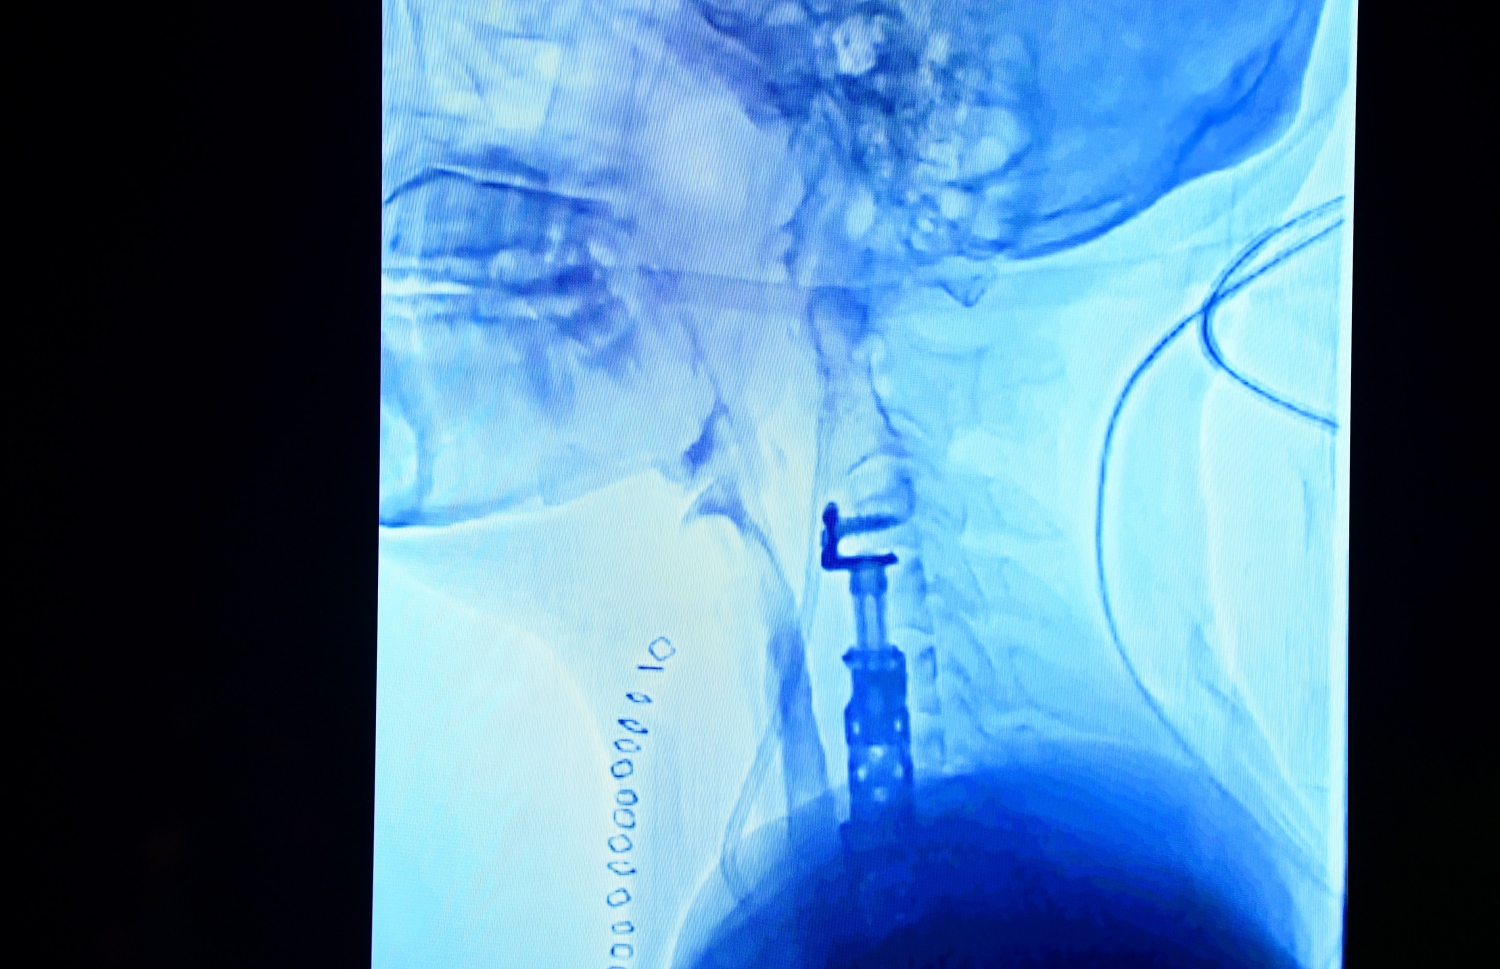

ދަގަނޑު ނެގުމަށް ފަހު، ނޭފަތާއި މަތީތައްޔާއި އަދި ނޭފަތުގެ ކަށިގަނޑަށް ލިބިފައި ހުރި ގެއްލުންތައް ރިޕެއާކުރުމުގެ މަސައްކަތް ޑޮކްޓަރުން ކުރެއްވި އެވެ. މައިބަދަ އަށް ލިބިފައި ހުރި ގެއްލުންތައް ފަސޭހަ ކުރުމަށް ވެސް ހާއްސަ އޮޕަރޭޝަނެއް ކުރެއްވި އެވެ. އަދި ފިޒިއޯތެރަޕީ އާއި ރިކަވަރީގެ އެހެނިހެން ފަރުވާތައް ވެސް އޭނާ އަށް އަންނަނީ ދެމުންނެވެ.

ހަށިގަނޑު ފޫއަޅުވާލައި، ދަގަނޑެއް ވަތް ބިދޭސީ މަސައްކަތު މީހާއާ ގުޅޭ މައުލޫމާތު ދިނުމަށް އޭޑީކޭ ހޮސްޕިޓަލުން ބޭއްވި ނިއުސް ކޮންފަރެންސްގައި ދެއްކި، އޭނާގެ ކަރުން މަތީގެ ސްކޭނެއް -- ފޮޓޯ: ފަޔާޒް މޫސާ | މިހާރު

"ވަރަށް ނަސީބުގަދަ، އެވަރު އަނިޔާއެއް، ކަނދުރާގެ ކުރިމަތިން އައިސް މައިބަދަ އަށް ވަތްއިރު، އެއްވެސް މައި ނާރަކަށް ގެއްލުމެއް ނުލިބޭ،" އެ ހޮސްޕިޓަލުގެ ނާރުގެ ޑޮކްޓަރު އަލީ ނިޔާފް ވިދާޅުވި އެވެ.